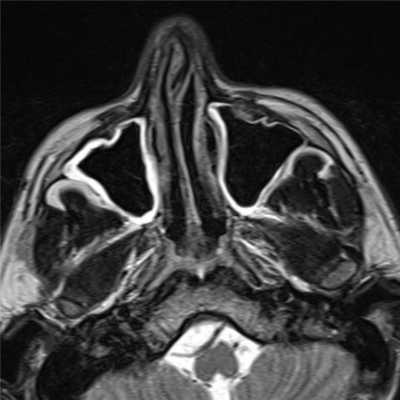

- КТ иМРТ придаточных пазух. При недостаточной информативности рентгенологической диагностики показана КТ лицевого скелета. Она дает возможность уточнить локализацию кисты, размеры ее полости. При наличии признаков сопутствующего поражения мягких тканей или развития осложнений используется магнитно-резонансная томография.

Рентгенологическое исследование при мукоцеле лобной пазухи определяет увеличение размеров пазухи, растяжение ее дна, уменьшение прозрачности. Возможно выпячивание перегородки между лобными пазухами в здоровую сторону. Прерывистость контуров лобной пазухи может указывать на наличие фистулы. Более точным и информативным исследованием является КТ лобной пазухи. Может применяться УЗИ и МРТ околоносовых пазух. В некоторых случаях для определения воздушности лобной пазухи проводится диафаноскопию. При затруднениях в диагностике мукоцеле лобной пазухи показана диагностическая пункция. Для определения проходимости лобно-носового канала производят зондирование лобной пазухи зондом Лансберга.